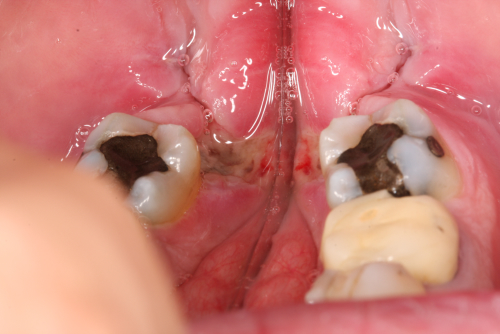

Depulpin 2 Veröffentlicht 30. Januar 2010 am 500 × 334 in Depulpin®-Einlage zur Devitalisierung eines Zahnes – Chronologischer Ablauf einer Knochen- und Schleimhautnekrose Devitalisierungsschaden Regio 38 Zustand nach drei Wochen.